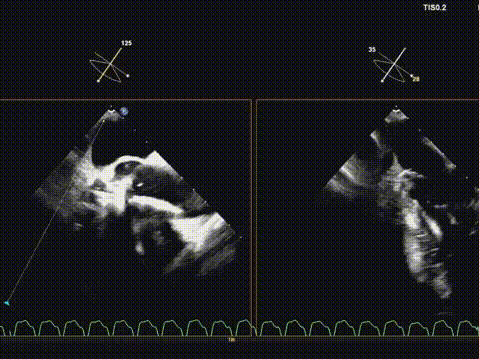

术后超声评估,瓣膜位置深度满意,形态可,微量瓣周漏,最大血流速度1.53m/s,平均跨瓣压差4mmHg。

华正东教授在术后总结中指出,全超声引导TAVR技术在避免放射线及造影剂相关肾损伤方面具有独特优势,特别适用于合并肾功能不全的高危患者。在本例手术中,超声影像清晰引导了导丝跨瓣、球囊预扩、瓣膜输送与释放等关键步骤,展现了其在复杂解剖条件下实现精准介入的可靠性。

术后超声提示人工瓣膜功能良好,平均跨瓣压差仅4mmHg,血流动力学改善显著。值得一提的是,术中选用的Evolut PRO瓣膜系统凭借其可回收、可重新定位的设计特点,为术中调整释放位置提供了重要技术支持,确保了瓣膜的稳定锚定与功能良好。此例手术的成功,充分展现了全超声引导TAVR在治疗二叶式主动脉瓣狭窄方面的可行性与安全性,为华中地区开展绿色介入技术积累了宝贵经验。